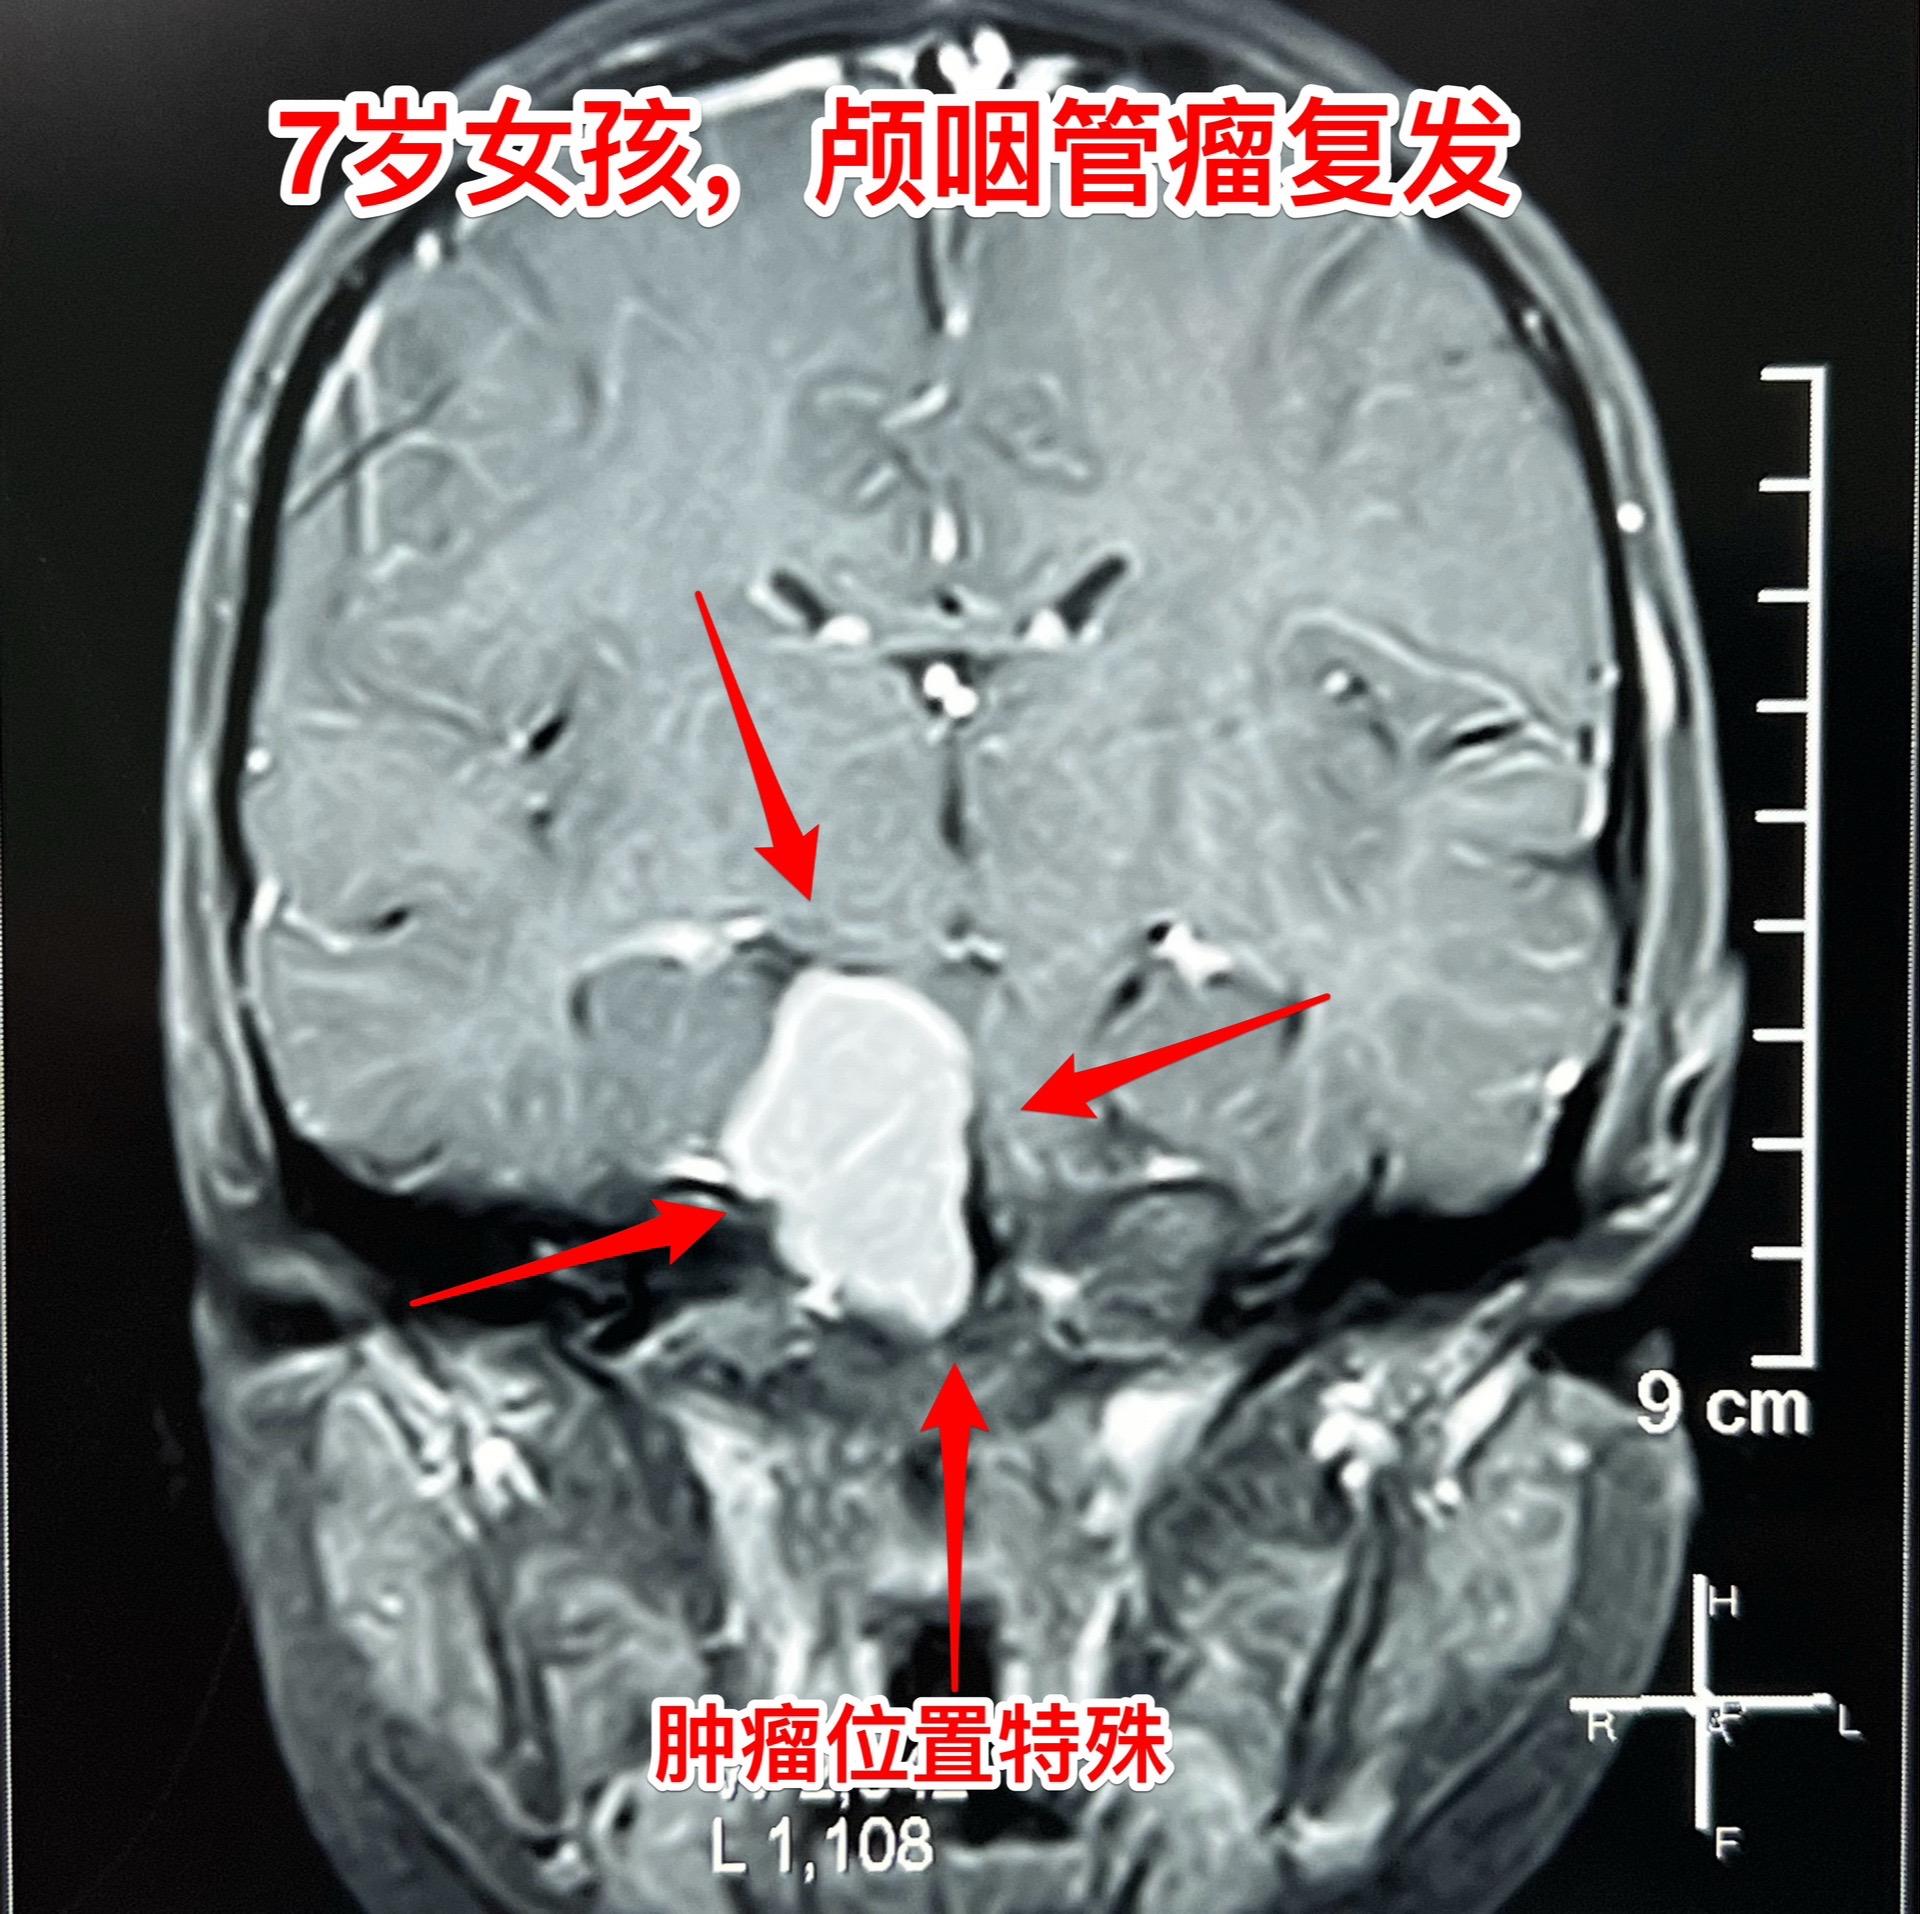

颅咽管瘤复发,看起来是一个瘤其实有三个。7岁女孩子,颅咽管瘤复发。从CT和磁共振来看,是一个大的囊性肿瘤,体积很大了,肿瘤向后颅窝生长,手术切除的难度还是比较大的。 2025年1月10日作手术过程中发现的情况比预想的还要复杂得多。除了这个大的囊性肿瘤之外还发现了两个孤立肿瘤。 这样的情况在我们科并不罕见,经常发现复发的颅咽管瘤病人脑部不止是一个瘤,有的时候有超过10个孤立的肿瘤。这种情况就要考验医生的技术和意志力了。当然,在我们科,总是争取把看见的瘤完全切除。